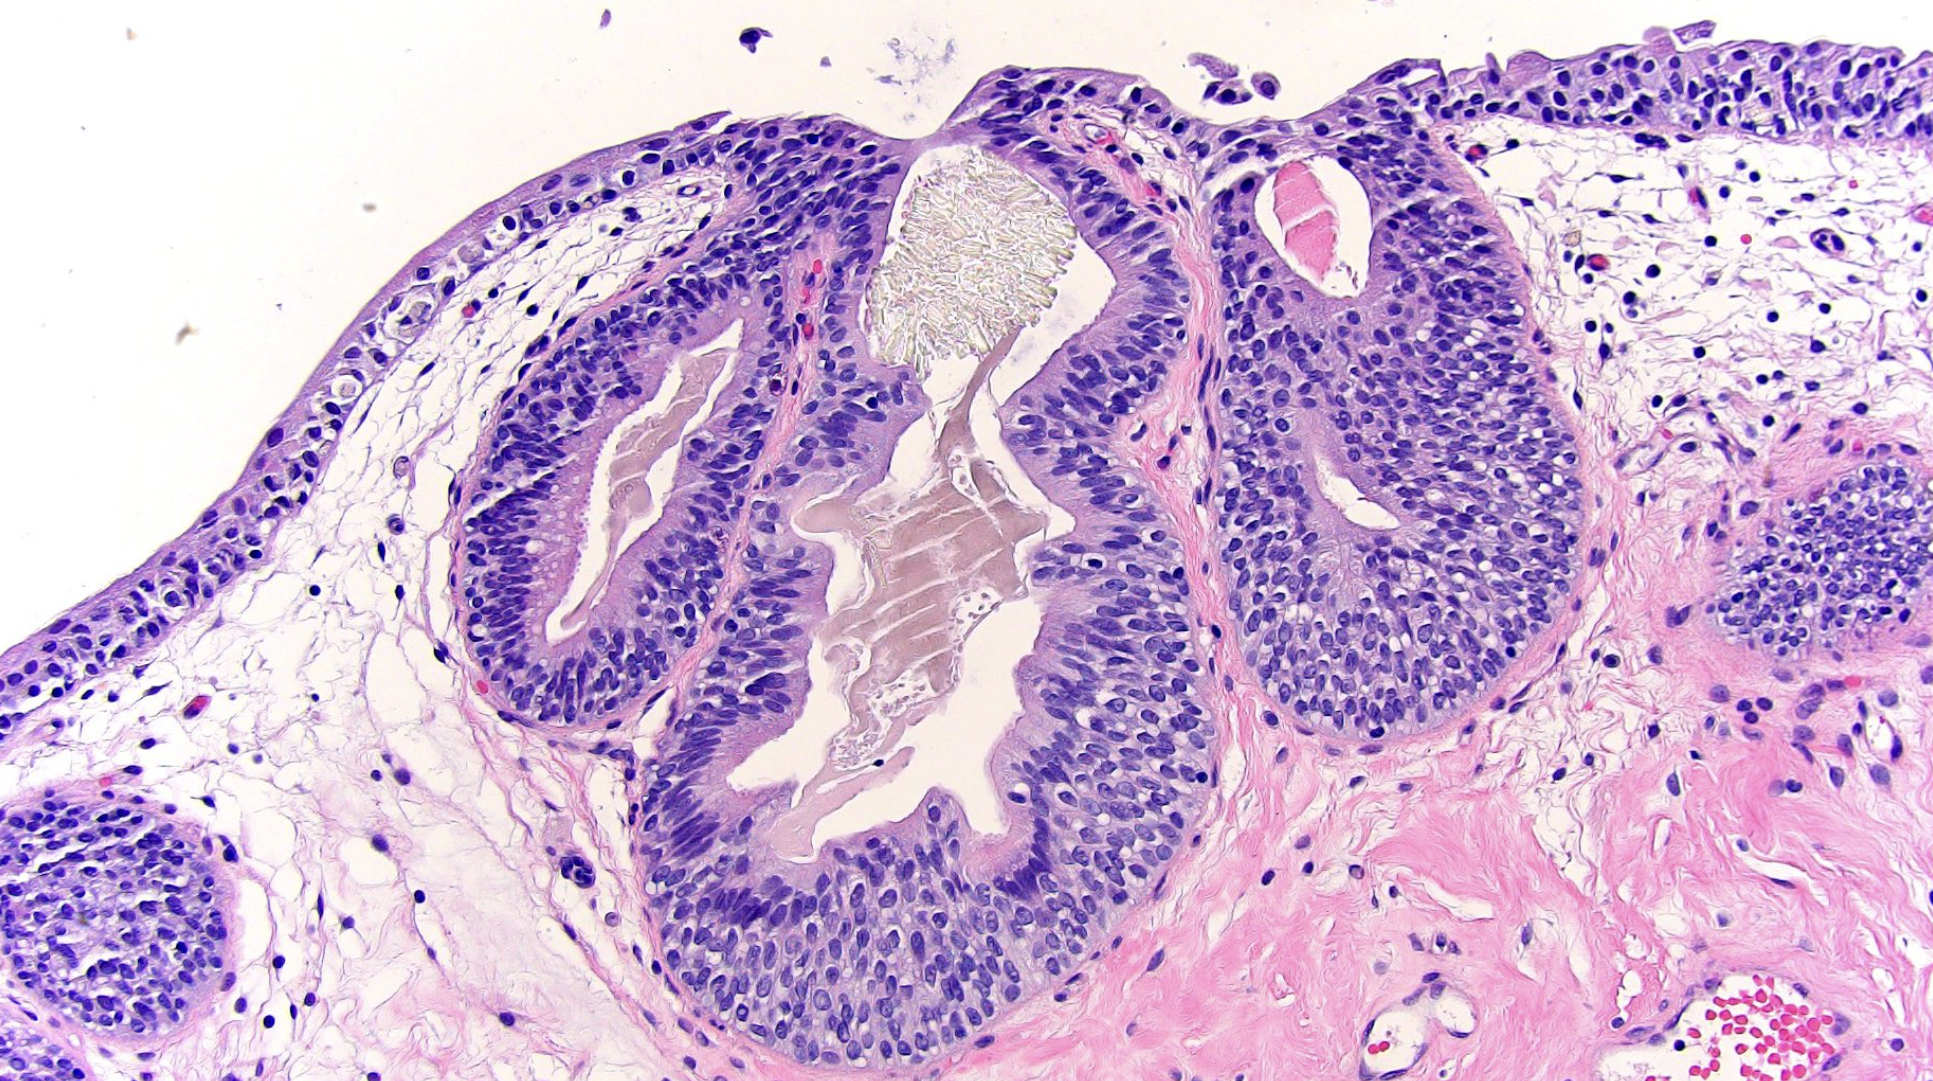

Below: Ureteral mucosa showing early cyst formation.

Source: Cystitis glandularis. Histology image. From “Bladder, ureter, and renal pelvis,” by L Durowoju and M Tretiakova. (2020), PathologyOutlines.com. https:// www.pathologyoutlines.com/topic/bladdercystitiscystica.html